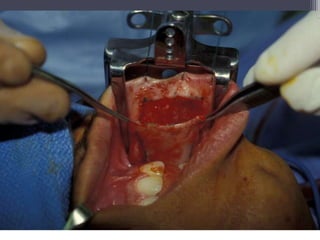

Case #2

Buccal Mucosal Urethroplasty

Dorsal Onlay